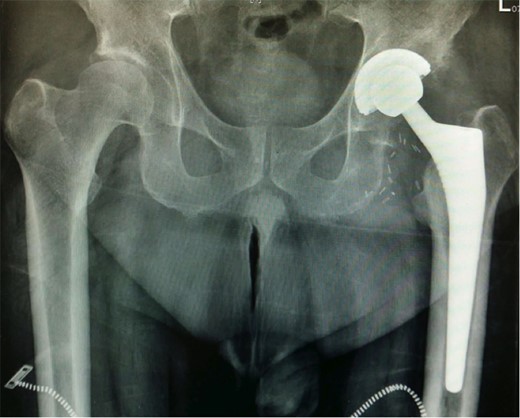

X-ray (Fig. 1) showed severe loss of joint space, subchondral cyst formation and sclerosis, confirming the clinical findings of advanced left hip osteoarthritis. Additionally, concomitant femoral head flattening was detected on X-ray, consistent with possible osteonecrosis.

Surgery was subsequently undertaken using hydroxyapatite-coated cementless femoral implant and corresponding modular acetabular component. (Fig. 2). The surgery was uneventful, peri-operative course without complication, and post-operative review showed a successful resolution of his symptoms. Intraoperatively, the excised femoral head was sent for screening for bone harvest.